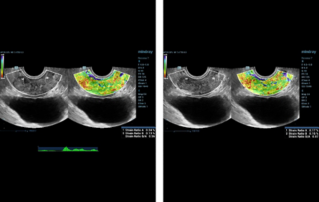

??????? ??? ?? ? ??? ??? ??? ?????, ?? ??(pelvic floor) ??? ??? ?? ??(??? ?/?? ??)? ??? ???. ? ?? ???? PVA, RVA ? PUA ?? 20┬░ ???? ?????. ? ?? ???? PVA ŌĆō 134o, RVA ŌĆō 82o ? PUA ŌĆō 119o.

??? ???? ??? ?? ????? ??? ??? ?? ?????. ????? ? ??? 30mm?? 42mm?? ??? ? ??? ??? ??? ????? ?? ? ? ?? ? ?? ? ?? ??? ??? ??? ? ????. ?? R ? ???? ?? ?? ?? ?? ?? 7mm, ?? ?? 8mm???.